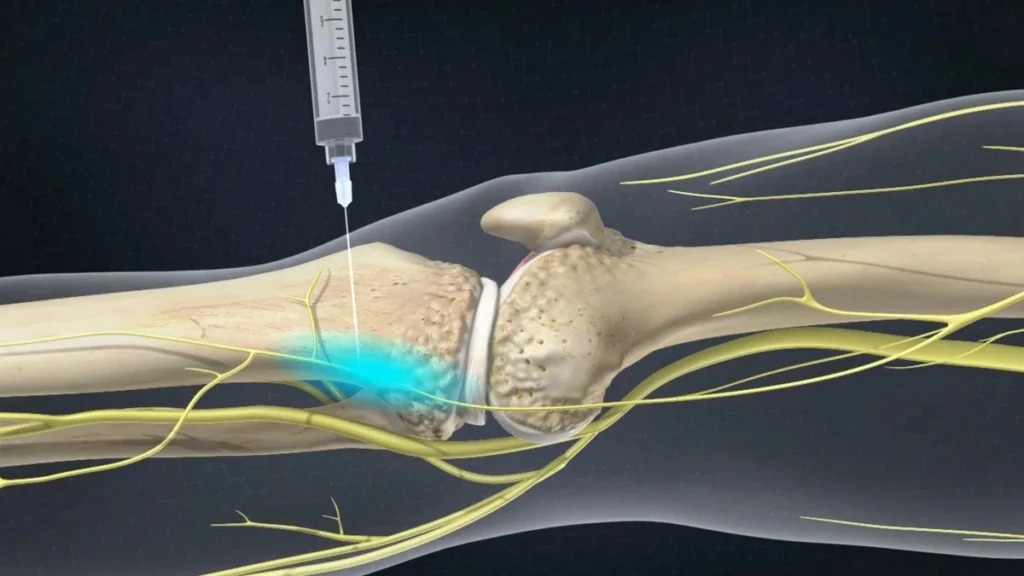

“Pain from osteoarthritis of the knee is not one thing. Instead, it is a blend of processes: inflammation, joint wear, stiffness, and nerves transmitting painful signals.” A genicular nerve block is a precise targeting of a “nerve highway,” which is “the road your pain messages are taking.”

The practitioner finds the major SP sites around the knee region. Under the guidance of image intensification (usually fluoroscopy or ultrasound), a small needle is directed at the site around the SPs. A small quantity of local anesthetic is administered. This temporarily stops the transmission of pain signals.

If your pain is being caused by your nerves, then relief will be apparent anywhere from a few minutes to an hour after your injections. As for how long relief will last, each person reacts differently. Some people feel relief for a few hours, while others experience extended levels of comfort.